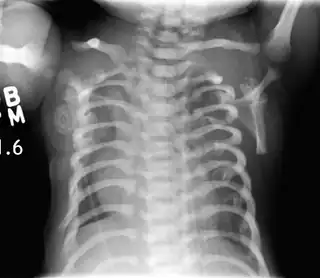

Distrofia torácica asfixiante

La distrofia torácica asfixiante (DTA), también llamada síndrome de Jeune, es una enfermedad hereditaria rara que se hereda según un patrón autosómico recesivo. Se incluye dentro del grupo de trastornos conocidos como osteocondrodisplasias por estar presente desde el nacimiento y afectar preferentemente al desarrollo de los huesos y cartílagos. La principal manifestación es un tórax estrecho y constreñido, lo que provoca insuficiencia respiratoria grave e infecciones pulmonares severas, otras manifestaciones son extremidades cortas, talla baja, anormalidades de la pelvis y los riñones. La mayor parte de los niños afectados mueren poco después del parto, aunque en algunas formas menos agresivas los pacientes tienen una expectativa de vida más larga. No existe tratamiento curativo, pero algunas técnicas quirúrgicas como la toracoplastia permiten mejorar los síntomas en ciertos casos. La distrofia torácica asfixiante es una de las enfermedades genéticas causadas por un mal funcionamiento del orgánulo intracelular denominado cilio primario, por ello se incluye dentro de las ciliopatías.[1][2]